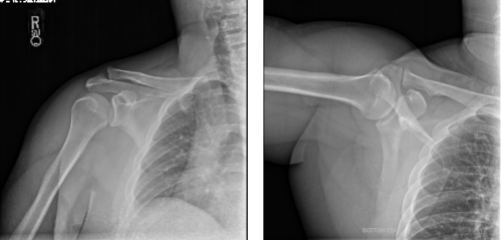

Patient presents shoulder & biceps pain from playing handball. He saw an increasing bulge of right biceps. He also presented his X-ray results, clearly showing the mild to moderate degenerative changes to the right acromioclavicular joint. By this time, we agreed to proceed with treatment options including Physical Therapy, Injection and MRI to identify the real condition of his shoulder.